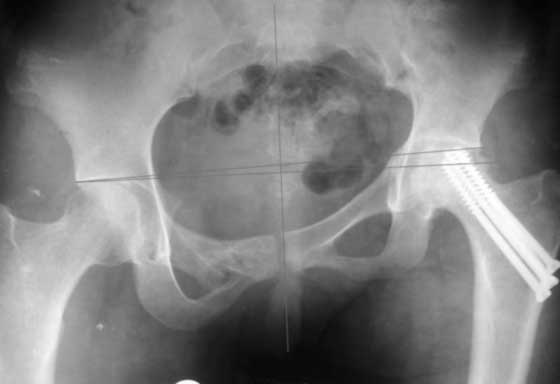

Приветствую! Положительный опыт есть. Первая попавшаяся презентация с похожим сращением.

Многое зависит от деталей видимых после кт и др проекций.

РАВ

По первым снимкам имеется сложная травма с переломом ацетабулума (видна линия перелома в задней колонне) и таза с ипсилатеральным переломом шейки. Не удалось репонировать крестцово-подвздошное сочленение, и смещение с ротацией осталось, особенно в верхней ветви лонной кости. Клинические снимки подтверждают остаточную деформацию и укорочение конечности за счет таза.

В зависимости от данных дополнительных исследований можно предложить операцию - создание опороспобного таза из двух этапов. Остеотомия таза слева через задний доступ на уровне крестцово-подвздошного сочленения и через передний доступ справа на уровне верхней и нижних ветвей лонной кости.

Неплохо было бы провести одномоментную репозицию и фиксацию, но после таких операции благодаря "мягкотканой памяти формы" очень часты осложнении - несостоятельность конструкции.

Двухэтапный вариант имеет преимущества, когда мягкие ткани адаптируются постепенно с помощью того же аппарата внешней фиксации таз-бедро или на скелетном вытяжении.

После достижения желаемого низведения фиксировать "пластиной балкой" сзади, и спереди реконструктивной длинной пластиной, включая симфиз.